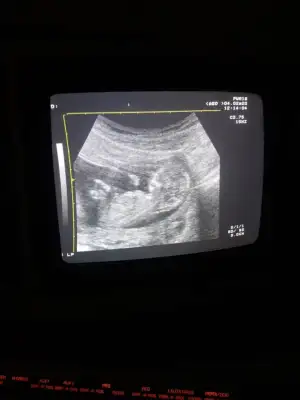

11 haftalikken kiz demistiniz ve Evet 18+4 te doktor kiz bebek dedi ☺Kız gibi diyorum net degil usg başka varmı 12+ hafta usgde paylaşın

Kız gibi tam net degil başka ush paylaşın 12 de olır13+1 sizce ?

Banda doğru tahmin ettiniz tebriklerGebelik haftanız 11 yazıyor bende 12+ istedim![]()

Başka usg varmı çok net değil diklik görünüyor sanki erkek gibi emin olamıyorum12 haftalık acaba cinsiyet tahmininde bulunabilir misiniz

Başka usg varmı çok net değil diklik görünüyor sanki erkek gibi emin olamıyorum

Yaa yukardan arkadaş bana mesaj yazıyorduYani şu gördüğüm nub ise dik görünüyor bacaklar yukarda nubunu değiştirmiyorsa pozisyon erkek gibiEki Görüntüle 2584968